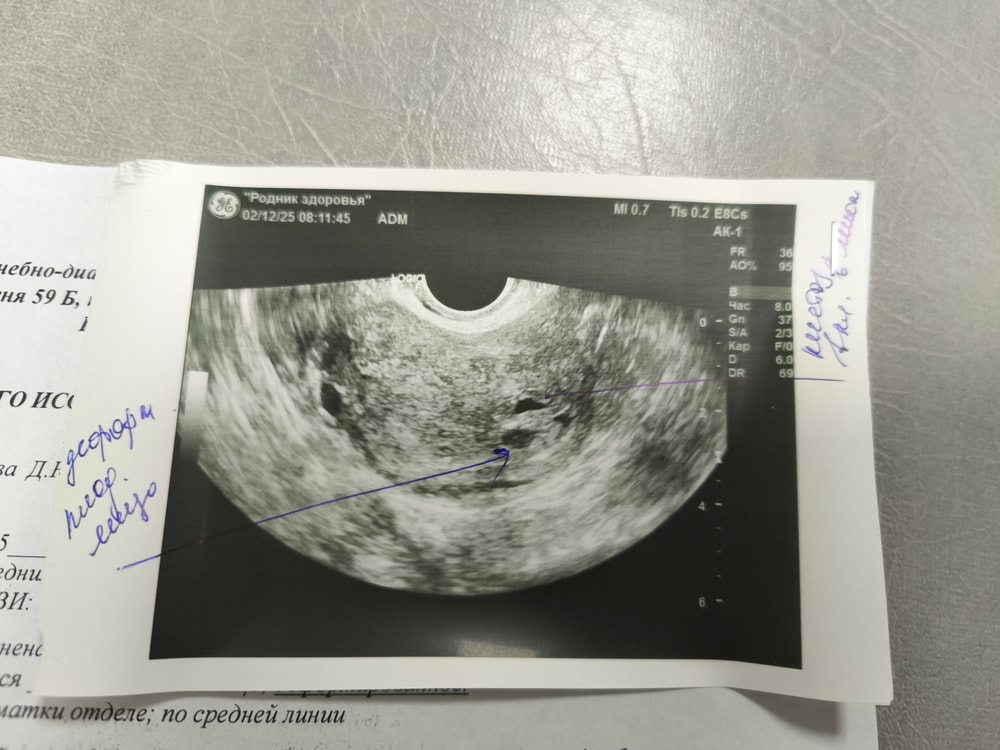

В первый день задержки якобы увидели пя, на узи пошла так как были бежевые выделения. В первый день задержки пя 4,5 мм, я очень сильно сомневаюсь что это было оно, так как овуляцию отслеживала по узи и была 10.11.25 а узи 24.11.25. Сегодня повторила через неделю, срок по месячным 5,2 н.пя 6,5мм деформация ,не выросло практически , отправляют на чистку нет желточного мешочка.Сравнивают с первым узи, но разные клиники. Прекреплю снимки. У меня аденомиоз. Могли первый раз перепутать, так они даже находятся в разных проекциях. Первый снимок в день задержки, ниже от сегодняшнего дня

Galina, я мало в этом разбираюсь. Но у меня при узи от 2.12 было очень деформировано, с ее слов. Она мне сказала без вариантов и в заключении написала замершая беременность. Через два дня 4.12 узи и плодное яйцо уже 10.5 т деформация не такая сильная и желточный мешочек